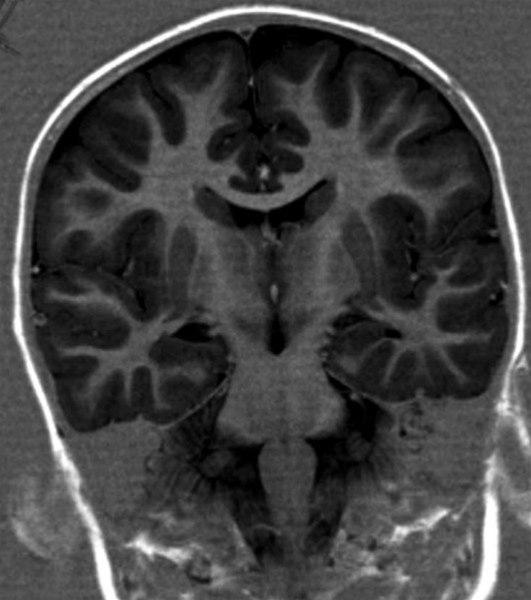

MS forandringer (MR koronalsnitt)

Små hvite flekker mange steder i hjernevevet er typisk for MS